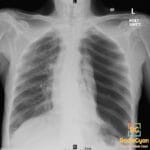

- Radiology Cases: Images with a to-the-point discussion highlighting the specific diagnostic criteria.

- Radiology Case of the Day Collection: Aunt-Minnie Board Cases for Rapid Review.

- Radiology Spotters: 700+ spot / “Aunt-Minnie” cases divided into sets of 10 each!